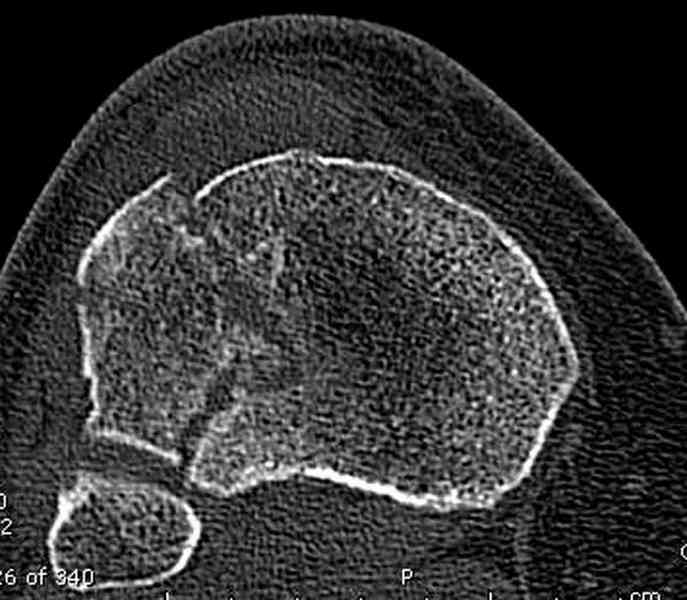

Для внутрисуставных переломов необходимо идеальное сопоставление, а такая задача без КТ срезов усложнится. Только КТ надо делать после дистракции сустава, иначе нельзя получить объективную информацию.

Основная задача в лечении околосуставных переломов является создание солидного базиса в субхондральной зоне. Пластина подпорка (Butress) или субхондральные перкутанные шурупы в виде плота (Raft) для ранних движении.

У больного двухстороннее повреждение, ограничен в нагрузке не менее 8-10 недель. После односторонней фиксации будет активным, хотя бы в пределах койки. Без спешки дождаться улучшения кожных покровов, и аппаратом Илизарова в комбинации с шурупами или спицами, из мини-доступов.